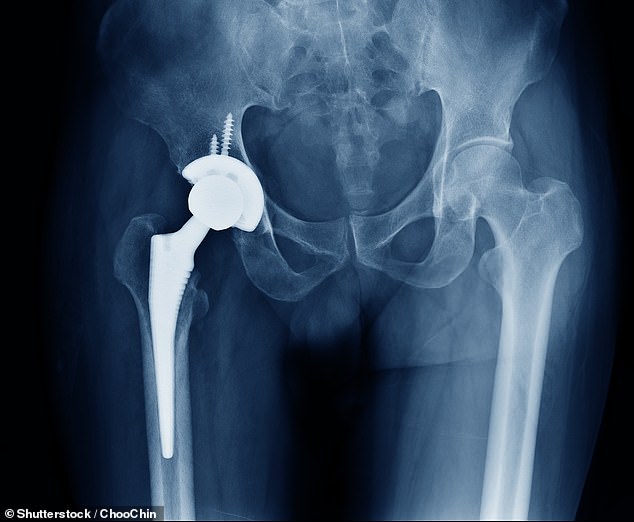

At the heart of the crisis lies a technological bottleneck. Bone cement, used in over 80% of knee replacements and 60% of hip procedures, is essential for securing implants and enabling patients to recover quickly. Heraeus, the NHS's preferred supplier, has warned of a two-month shortage due to its system upgrade. While alternative manufacturers exist, experts like Dr. Alex Dickinson of the University of Southampton emphasize that no substitute can replicate the material's properties without extensive testing. 'Implant engineering is a cautious process,' he explains, 'and new technologies carry risks that require years of follow-up to understand.'